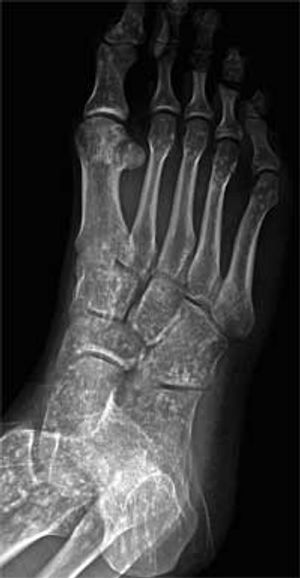

A 21-year-old man presented for evaluation after he sprained his right ankle while hiking. Radiographs of the ankle showed no fractures but revealed diffuse sclerotic lesions in most of the visualized bones.